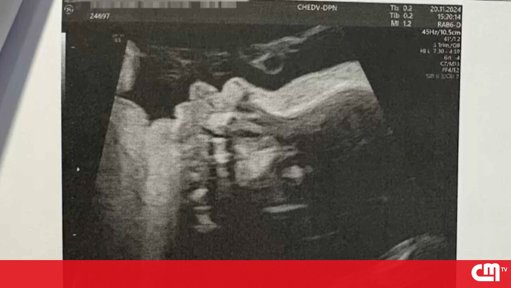

Segundo o seu relato, quando se deslocou ao hospital com queixas, foi informada da morte do feto.

O relatório da autópsia, segundo a família, terá apontado para problemas cardíacos no bebé que nunca haviam sido reportados à mãe durante a gestação.